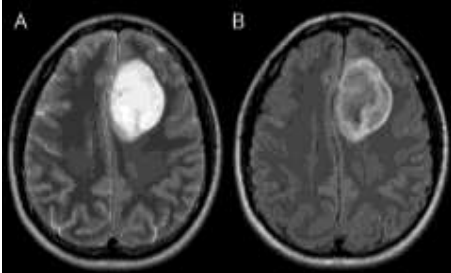

Durante a avaliação de uma ressonância magnética de um paciente com um tumor de origem glial recidivado (já diagnosticado por histopatologia), o radiologista se depara com o seguinte aspecto de imagem na avaliação das sequencias T2 e Flair.

Analise a importância do achado de imagem e assinale a alternativa correta.